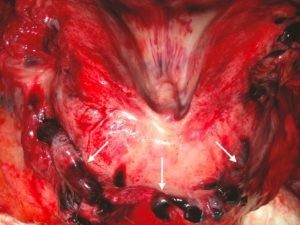

Pulmões com aparência impressionante

Os pulmões eram frequentemente pesados, atingindo um peso de 3420 gramas em um paciente. Nos pacientes autopsiados, o peso médio do pulmão era de cerca de 1990 gramas, sabendo que normalmente é de cerca de 840 gramas em homens e 640 gramas em mulheres.

A superfície externa dos pulmões apresentava aparência variegada, com áreas pálidas alternadas com outras levemente salientes e firmes, muito ricas em capilares e de cor azul avermelhada. “Essas mudanças grosseiras em nossa série de autópsias são impressionantes e explicam as dificuldades em ventilar suficientemente a maioria desses pacientes” , afirma Dominic Wichmann, Jan-Peter Sperhake e seus colegas.

A consistência do tecido pulmonar era firme, mas quebradiça. Em oito dos doze casos, essas alterações afetaram todas as partes dos pulmões. A aparência externa dos outros órgãos era normal, com exceção do baço, que parecia ser afetado pela infecção viral em três pacientes.